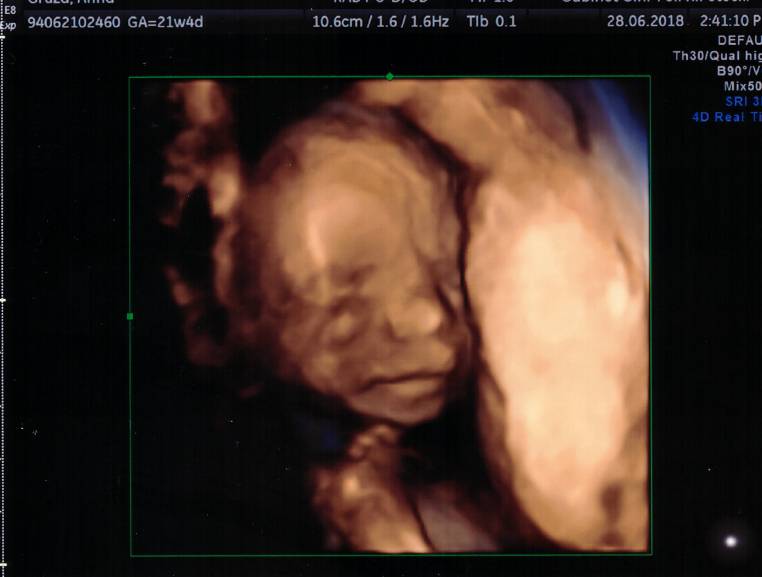

Maleństwo ma długą kość udową, czyli przewiduję, że będzie wysokie jak ojciec, bo też ma długie nogi... jak modelka. Serducho ok, ale tak się ułożyło, że ciężko było ujrzeć, ale się udało. Główka super, ilość wód płodowych również, przezierność też zbadana i także dobrze.. wszystko pomierzone, jest fajnie, tylko z takim ułożeniem był problem żeby zerknąć na nóżki, żeby wykluczyć szpotawość. Ale lekarz mówi że ok [emoji2]

No i... leżymy, głowica lata po brzuchu, ja widzę jak maleństwo kopie, czuję to wszystko więc wrażenia po prostu nie do opisania..[emoji7] I lekarz mówi bardzo poważnie "Chcą Państwo wiedzieć?". My odpowiadamy, że pewnie. A on pyta, kto jak w rodzinie obstawia... to mówię, że tu większość na dziewczynkę, narzeczony na chłopca.[emoji5]

"Tutaj jest siusiak"

Pierwsze, co pomyślałam - Mój Boże, to Jan.

Kurczę, będę miała syna. [emoji2] Narzeczony mokre oczy, ja już gadam po imieniu, lekarz również się śmieje, po podłapał... normalnie jestem w szoku. Aaale jaki piękny portet mam! Jaki ten mój syn kochany, bo wtulony w mamusię, lubiący Pana doktora, bo wierzgał niesamowicie.

Maaaaam syyyyna [emoji7] [emoji7] [emoji7] [emoji7]

Pochwalcie się co u Was po wizytach, trzymam kciuki![emoji8] [emoji7] Zobacz załącznik 871972

W ogóle zazdroszczę Wam tych zdjęć 3d, sam Wam lekarz włącza taki obraz, czy prosicie?

Mój lekarz jest pasjonatem usg sam włącza.

Tu włączył bo młody był tak ułożony że nie bardzo było widać, a chciał zobaczyć czy nie ma rozszczepu wargi.

Ale jak był młodszy też mi zrobił fotki 3d.

Nie płacę za to dodatkowo